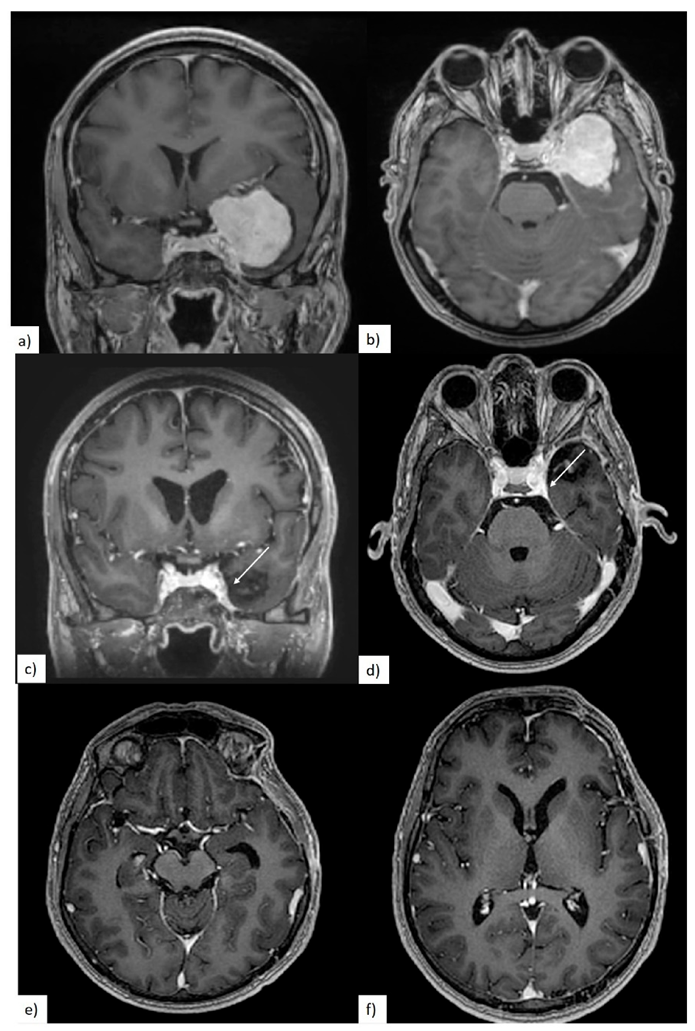

3.2. Preoperative Clinical and Radiological Data